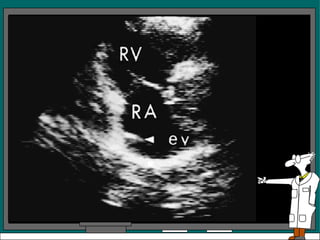

El ventrículo derecho y la válvula tricúspide también se pueden registrar con el transductor en la posición paraesternal, el plano del examen no se ajusta exactamente ni al eje largo ni al eje corto Este estudio muestra el tracto de entrada del VD y además brinda la oportunidad de registrar el movimiento de la válvula tricúspide.

Variantes normales: Banda moderadora prominente en VD Estructura filamentosa fina que atraviesa la cavidad del VI: Cuerdas tendinosas falsas Valvula de Eustaquio prominente en la AD en su union con la vena cava inferior se ve en paraesternal eje largo y en vista de 4 cámaras apical y subcostal. Ecos filamentosos dentro de AI, pueden originarse a partir del tejido residual que representa a la red de Chiari Septum con forma de S o  sigmoide con protrusion dentro del tracto de salida